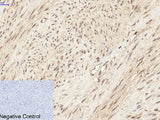

Phospho-ERK 1/2 (Tyr204) Polyclonal Antibody

Applications WB,  IHC-p,  IF

IHC 1:100-1:300